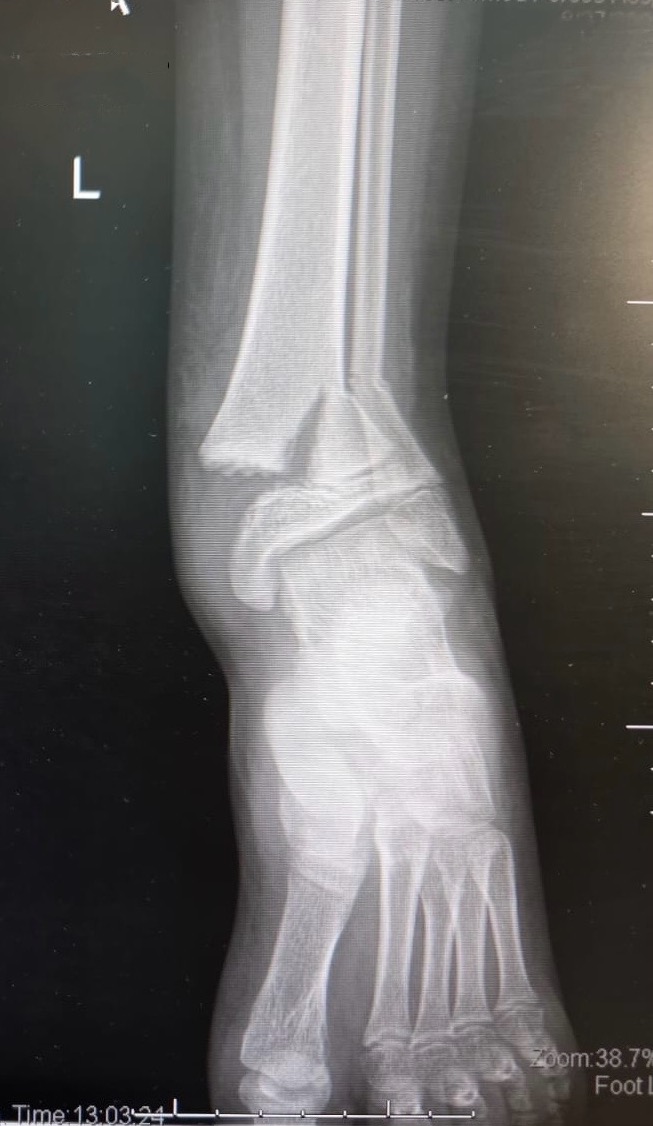

• Medical records of patients with documented FCS from May 2007 to January 2009 were retrospectively reviewed. Consecutive, matched control patients were identified based on similar hindfoot, mid-foot and/or forefoot injuries who did not undergo foot fasciotomy during the same period. The primary outcomes analysed were the development of claw or hammer toes and neuropathic pain.

• 19 patients with foot fasctiotomies were identified and matched with 19 controls. Median follow-up was 19.5 months (range, 3.5-47.5 months) for the combined cohorts. The most common mechanism of injury was an explosive blast. Nine fasciotomy and nine control patients sustained open foot fractures. Significantly more patients with foot fasciotomies developed claw toes (50% vs 17%, p=0.03). There were no significant differences in the development of neuropathic pain, sensory deficits, motor deficits, chronic pain, stiffness or infection. The fasciotomy patients underwent an average of 5.5 surgeries per patient versus 4 surgeries per patient in the control group.